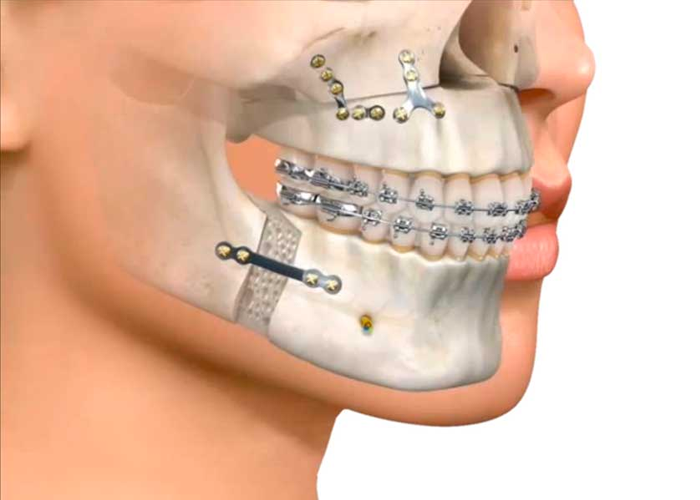

El tratamiento de grandes tumores mandibulares, reemplazos de la articulación temporo mandibular (ATM) por disfunciones avanzadas, u otras patologías conlleva a la resección quirúrgica mandibular en bloque de un segmento, así como secuelas de infecciones y trauma de alta energía. Situaciones clínicas que ocasionan una alteración anatómica y funcional del paciente con implicaciones estético-funcionales que necesitan meticulosidad en la reconstrucción de los defectos con la combinación de injertos óseos libres, prótesis de ATM, distracción ósea e implantes cigomáticos